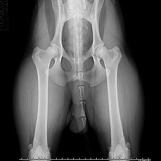

Hip Dysplasia in Dogs

What Is Hip Dysplasia in Dogs and Puppies?

Hip dysplasia is a condition that occurs during the growth stage in dogs. It results in hip joints that don't fit together well and are looser than normal.